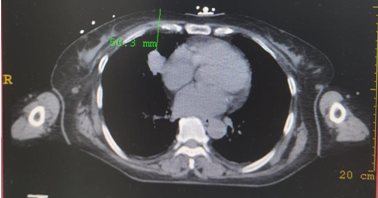

病例简介:一例小肠间质瘤伴右肺结节患者

拟行:IQQA-Guide导航下右肺穿刺活检术

▲上图:IQQA-Guide术中全程三维量化实时定位、跟踪、引导及监控,辅助医生精准穿刺